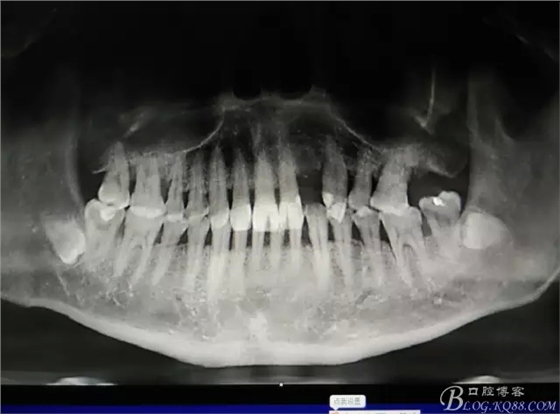

圖1.術(shù)前的CBCT檢查:22缺失。